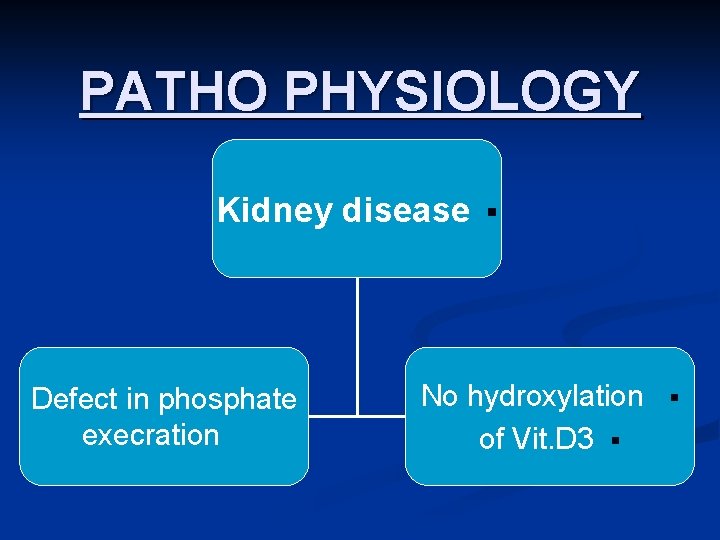

PATHO PHYSIOLOGY Kidney disease Defect in phosphate execration § No hydroxylation of Vit. D 3 § §